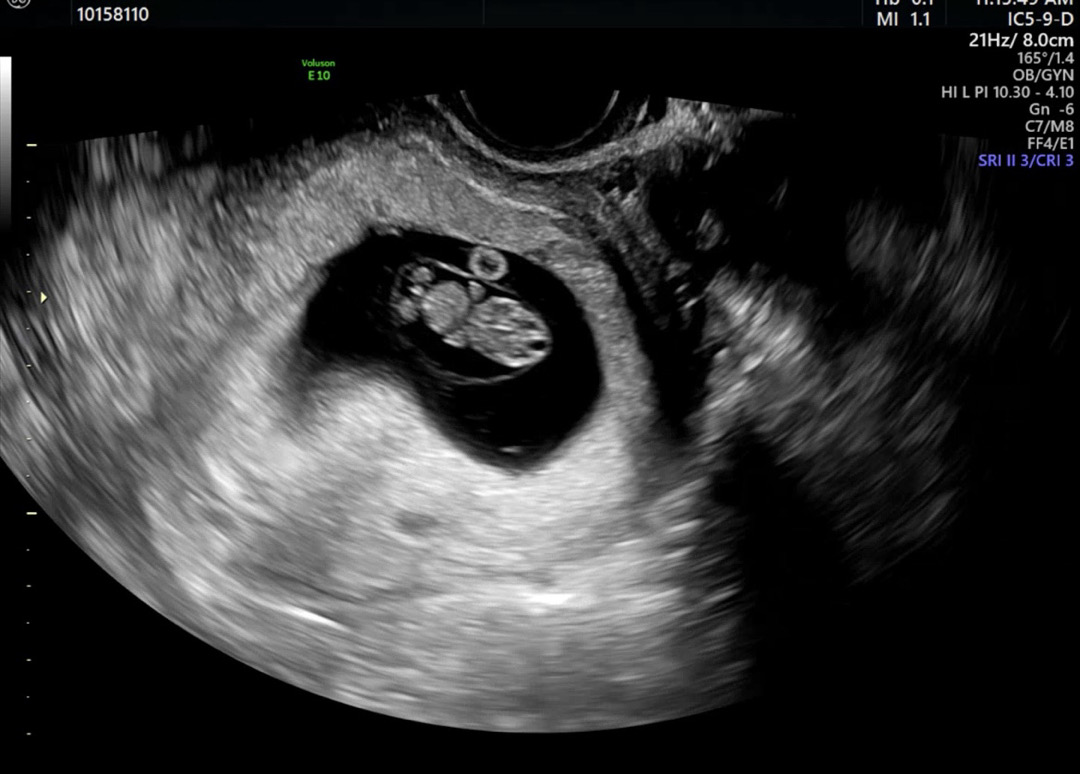

9주인데 자꾸 고추가 보여요.. 꼬리겠지만.. ㅎㅎ난황위치도 가운데같고.. 심장소리도 기차같은데.. 자꾸 고추가 보이고.. 아들일까요? 딸이신분들 초음파에서도 저렇게 보이셨을까요?

아마 탯줄일거에요! 아직 성기가 발달할 시기가 아니라서요 ㅎㅎ 현재는 여아남아 모두 같은 형태로 가지고 있다고 합니다!